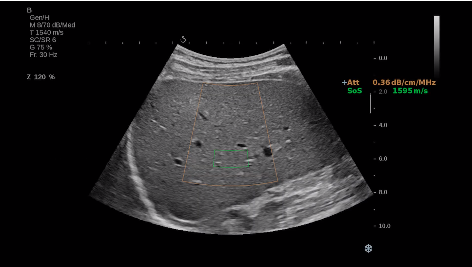

法國聲科影像(SuperSonic Imagine,SSI. Euroniex:FR0010526814)近日發(fā)表公告,宣布其研發(fā)的新一代“極速”超聲成像平臺(UltraFast Imaging),首次實現(xiàn)了肝臟的多項超聲定量評估新指標(biāo)同步檢測,包括:Att PLUS,SSp PLUS和Vi PLUS等,基本涵蓋肝臟相關(guān)病理變化指征的如纖維化、脂肪變、炎癥等。據(jù)悉,此多項新技術(shù)新將搭載于新Aixplorer系列E超系統(tǒng)。

E超相關(guān)技術(shù)已被多項多中心大樣本研究證實對于肝纖維化無創(chuàng)評估有重要意義,同時也可全面應(yīng)用于乳腺、甲狀腺、肝臟、前列腺、肌骨、婦科等全身各組織器官的定量評估和鑒別診斷。在慢性肝臟方面,聲科E超的肝臟相關(guān)定量診斷技術(shù)集,于2018年獲得美國FDA認(rèn)證,成為FDA歷史上首次獲批的單病種超聲全面定量解決方案。